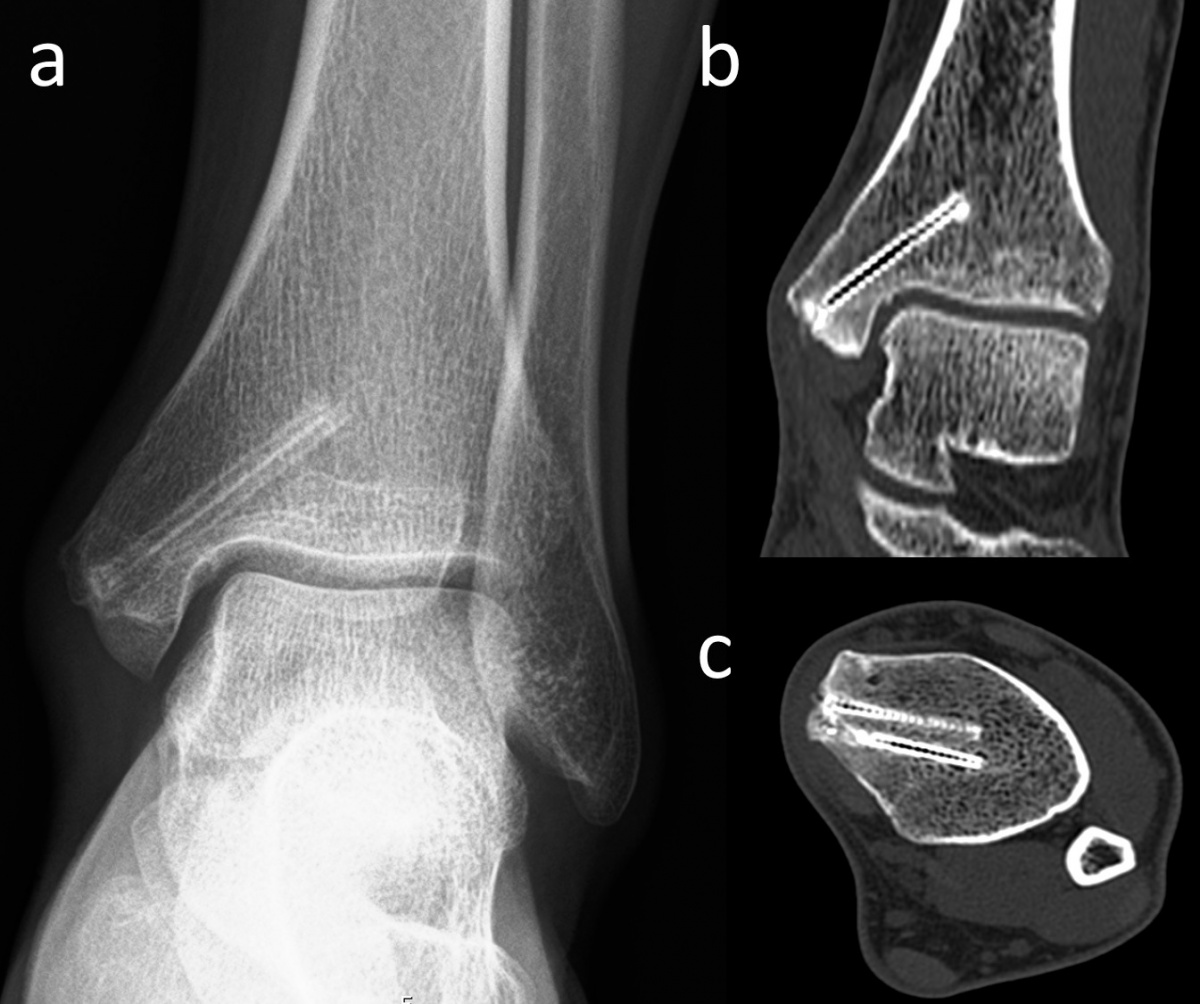

In Bezug auf die Gasbildung und Resorption zeigt die Computertomographie ähnliche Ergebnisse wie die konventionellen Röntgenaufnahmen. In der Frühphase sind sowohl die Schrauben als auch die umgebenden Gasansammlungen deutlich sichtbar (Abbildung 5). Langfristige CT-Untersuchungen zeigen, dass das Gas vollständig resorbiert wird und damit vollständig verschwindet. Die Schrauben sind bis zu ihrer Umwandlung in kortikales Knochengewebe deutlich erkennbar (Abbildung 6). Adil et al. haben nachgewiesen, dass diese Konturen vier Jahre nach der Implantation in der tomographischen Dichtemessung ähnliche Hounsfield-Einheiten aufweisen wie die umgebende Kortikalis (17). Darüber hinaus erzeugen Implantate auf Magnesiumbasis – im Gegensatz zu konventionellen Metallimplantaten wie Titanschrauben – nur minimale Metallartefakte (18-20). Für die Nachbeobachtung der Patienten stellt dies einen signifikanten Vorteil dar.

Magnesiumschrauben fixiert wurde. (a) In der anterior-posterioren

Röntgenaufnahme des Knöchels in Monat 30 nach der Operation sind

die Heilung der Fraktur und die Umrisse der Schrauben sichtbar. (b)

Koronare und (c) axiale CT-Aufnahmen weisen keine Gasansammlung

im Knochen auf und die Schrauben zeigen eine ähnliche Dichte wie die

umgebende Kortikalis.

Läsion am Talus einer Innenknöchel-Osteotomie und Mosaikplastik

unterzogen wurde. Die biplanare Innenknöchel-Osteotomie

wurde mit zwei Magnesiumschrauben fixiert. (a) Die anterior-posteriore

Röntgenaufnahme des Knöchels am 7. postoperativen Tag zeigt an

der Operationsstelle diffuse Gasansammlungen im Weichgebe (weiße

Pfeile). (b) Koronare und (c) axiale CT-Aufnahmen mit sichtbarem Gas

(weiße Pfeile).